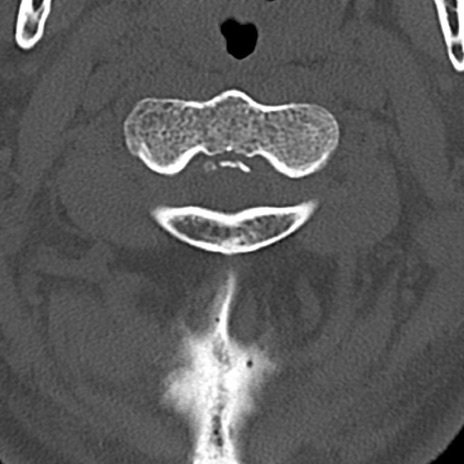

頚椎CT

矢状断像